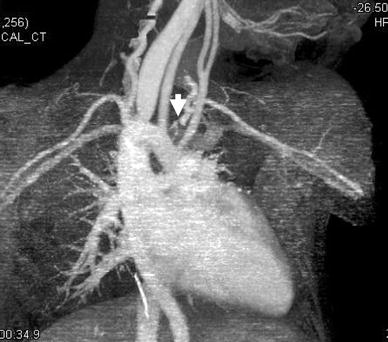

Preoperative three-dimensional computed tomography angiogram showing the right aortic arch with an isolated left subclavian artery (arrow)